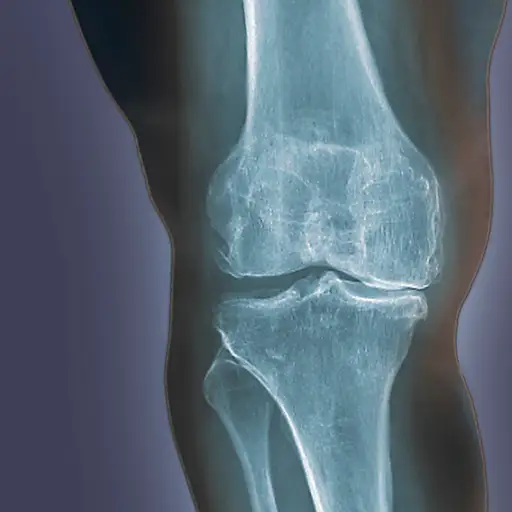

当你的骨骼之间的软骨作为垫子开始崩溃时,骨骼开始摩擦骨骼,它会导致骨关节炎,或关节疼痛肿胀。OA可以在早上和某些活动期间或之后疼痛和疼痛和痛苦引起僵硬。根据关节炎基础,OA是最常见的关节炎类型。通常,当您听到有人谈论普通的“关节炎时,OA就是他们的意思。大多数有OA的人在50年代发展条件,但其他人可以因受伤或肥胖而得到它。